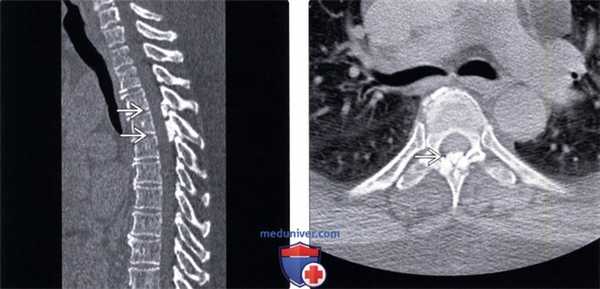

(Слева) КТ, сагиттальный срез: фокальная кальцификация желтых связок на двух уровнях среднегрудного отдела позвоночника. Значимого стеноза спинномозгового канала на фоне этих изменений не отмечается.

(Справа) КТ, аксиальный срез: фокальная срединная кальцификация желтой связки среднегрудного позвоночного сегмента. Эти изменения стали случайной находкой, поскольку клиники объемного воздействия на дуральный мешок или метаболических нарушений (например, пирофосфатной артропатии) у пациента не было.1. Дегенеративное поражение дугоотростчатых суставов: